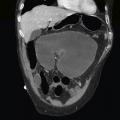

Volvulus du cæcum sur une coupe frontale de tomodensitométrie

ADULTE

OCCLUSION INTESTINALE